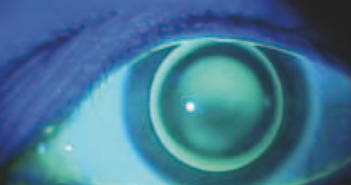

Les manifestations du kératocône au stade avancé sont aisément détectables à l’examen biomicroscopique : l’amincissement paracentral inférieur, la présence d’opacités stromales sous-épithéliales, la constatation de stries descémétiques sont autant de signes classiques de la maladie, qui viendront étayer une suspicion née du recueil de l’anamnèse d’un jeune patient présentant une réduction de l’acuité visuelle et un astigmatisme évolutif. Ces anomalies peuvent être enregistrées en tant que clichés photographiques au moyen d’une simple lampe à fente équipée d’un appareil photo numérique ; ces clichés constituent l’imagerie la plus directe d’un kératocône, mais requièrent que celui-ci ait atteint un stade particulièrement évolué ou compliqué. De plus, ils ne fournissent guère d’éléments quantitatifs ou fonctionnels pour le clinicien. Le recours à diverses techniques d’imagerie plus sophistiquées permet cependant d’évoquer le diagnostic du kératocône dès les stades précoces de l’affection, et d’en quantifier le stade évolutif.